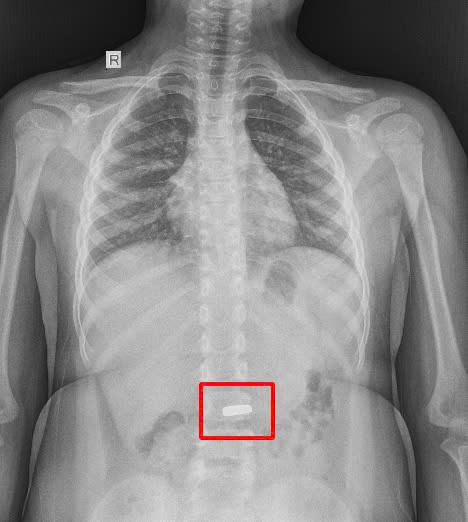

Tại bệnh viện, bé được thăm khám và chụp X-quang. Hình ảnh ghi nhận trong dạ dày có dị vật là nam châm với cạnh dài khoảng 20mm.

Hình ảnh X-Quang cho thấy dị vật giống như 1 nam châm